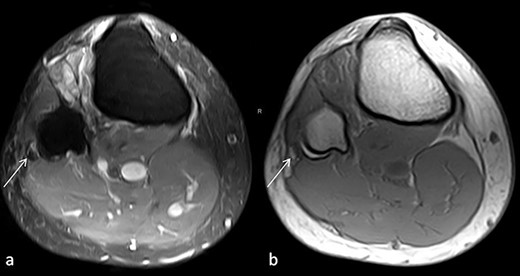

On clinical examination, the patient showed a weakness in dorsiflexion (Janda 3/5) and the great toe extension (0/5) as well as eversion weakness (3/5) on the right foot. A hypaesthesia was present in the corresponding area of the deep and superficial branch of the peroneal nerve with a positive Tinel’s sign in the area of the right fibula head. An MRI of the right knee and lower leg showed a discrete swelling of the common peroneal nerve and a slight hyperintense signal in T1-weighted images, which could not be further specified (Fig. 1). Motor nerve conduction studies showed a drop in amplitude across the fibular head and a slowed conduction velocity.

(a) Proton density, fat-saturated-weighted (PD FAT SAT) axial image: the arrow marks the swollen, hypointense peroneal nerve at the level of fibular head. (b) T1-weighted axial image: the arrow tags a hyperintense lesion in position of the peroneal nerve that may correspond to the intraneural haemorrhage.